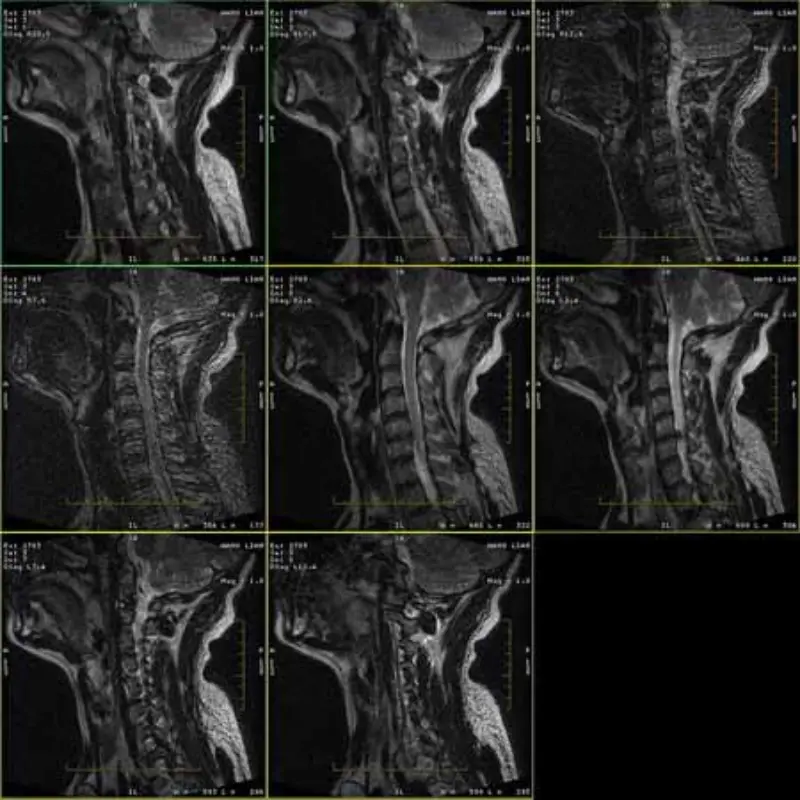

एफआरएफएसई और जीआरई प्रोटोकॉल की छवियों में भूत और कभी-कभी कम एसएनआर छवियां एक श्रृंखला में दिखाई देती हैं। लेकिन एसई प्रोटोकॉल छवियां सामान्य हैं।

कृपया संलग्न छवियाँ देखें।